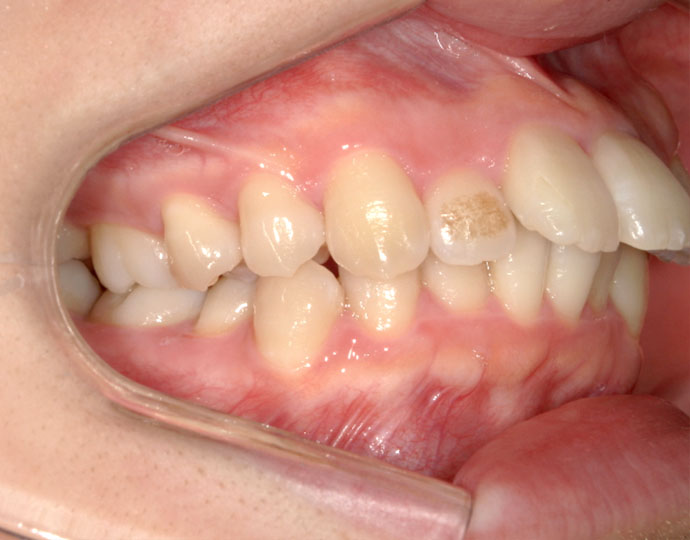

ワイヤー治療 叢生+上顎前突不正咬合 治療例

治療前

| 患者様 | 女性 19歳 |

| 主訴 | 歯並びと口元を綺麗にしたい。 |

| 診断 | 叢生歯列を伴う上顎前突不正咬合 |

| 治療方針 | 上顎左右第一小臼歯、下顎左右第二小臼歯の抜歯 |

| 治療に使用した装置 | セルフライゲーションブラケット インプラントアンカースクリュー×2 |

| 治療期間 | 2年6カ月 |

| 治療回数 | 24回 |

| 治療費(自費診療) | 880,000円(税込み) |